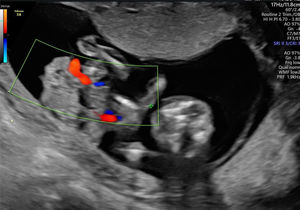

En la ecografía realizada al día siguiente en la consulta se objetivó un feto único en situación transversa izquierda con movimientos cardíacos fetales positivos. Se visualizó un encefalocele occipital de gran tamaño (fig. 1), con un defecto de la calota a nivel occipital y herniación importante de las estructuras cerebrales. En el extremo del encefalocele se objetivó una banda amniótica conectada al amnios (fig. 2). Asimismo, presentaba una ectopia cordis, con un importante defecto de la formación de la pared torácica anterior, ubicándose el corazón en el exterior de la caja torácica. En el estudio del corazón se visualizó que presentaba hipoplasia del ventrículo izquierdo. También se observó un gran defecto a nivel de la pared abdominal anterior, presentando gastrosquisis de gran cantidad de asas de intestino delgado y gran parte del hígado (fig. 3). Por último, a nivel de la columna se visualizó una cifoescoliosis severa a nivel lumbar (fig. 4). A nivel de placenta y anejos, la placenta se encontraba insertada en la cara anterior del útero con ecogenicidad acorde a la edad gestacional. En lo referente al amnios, este presentaba un fallo en la fusión con el corion (fig. 5). La cantidad de líquido amniótico era normal. No se encontraron otros hallazgos en la exploración ecográfica.